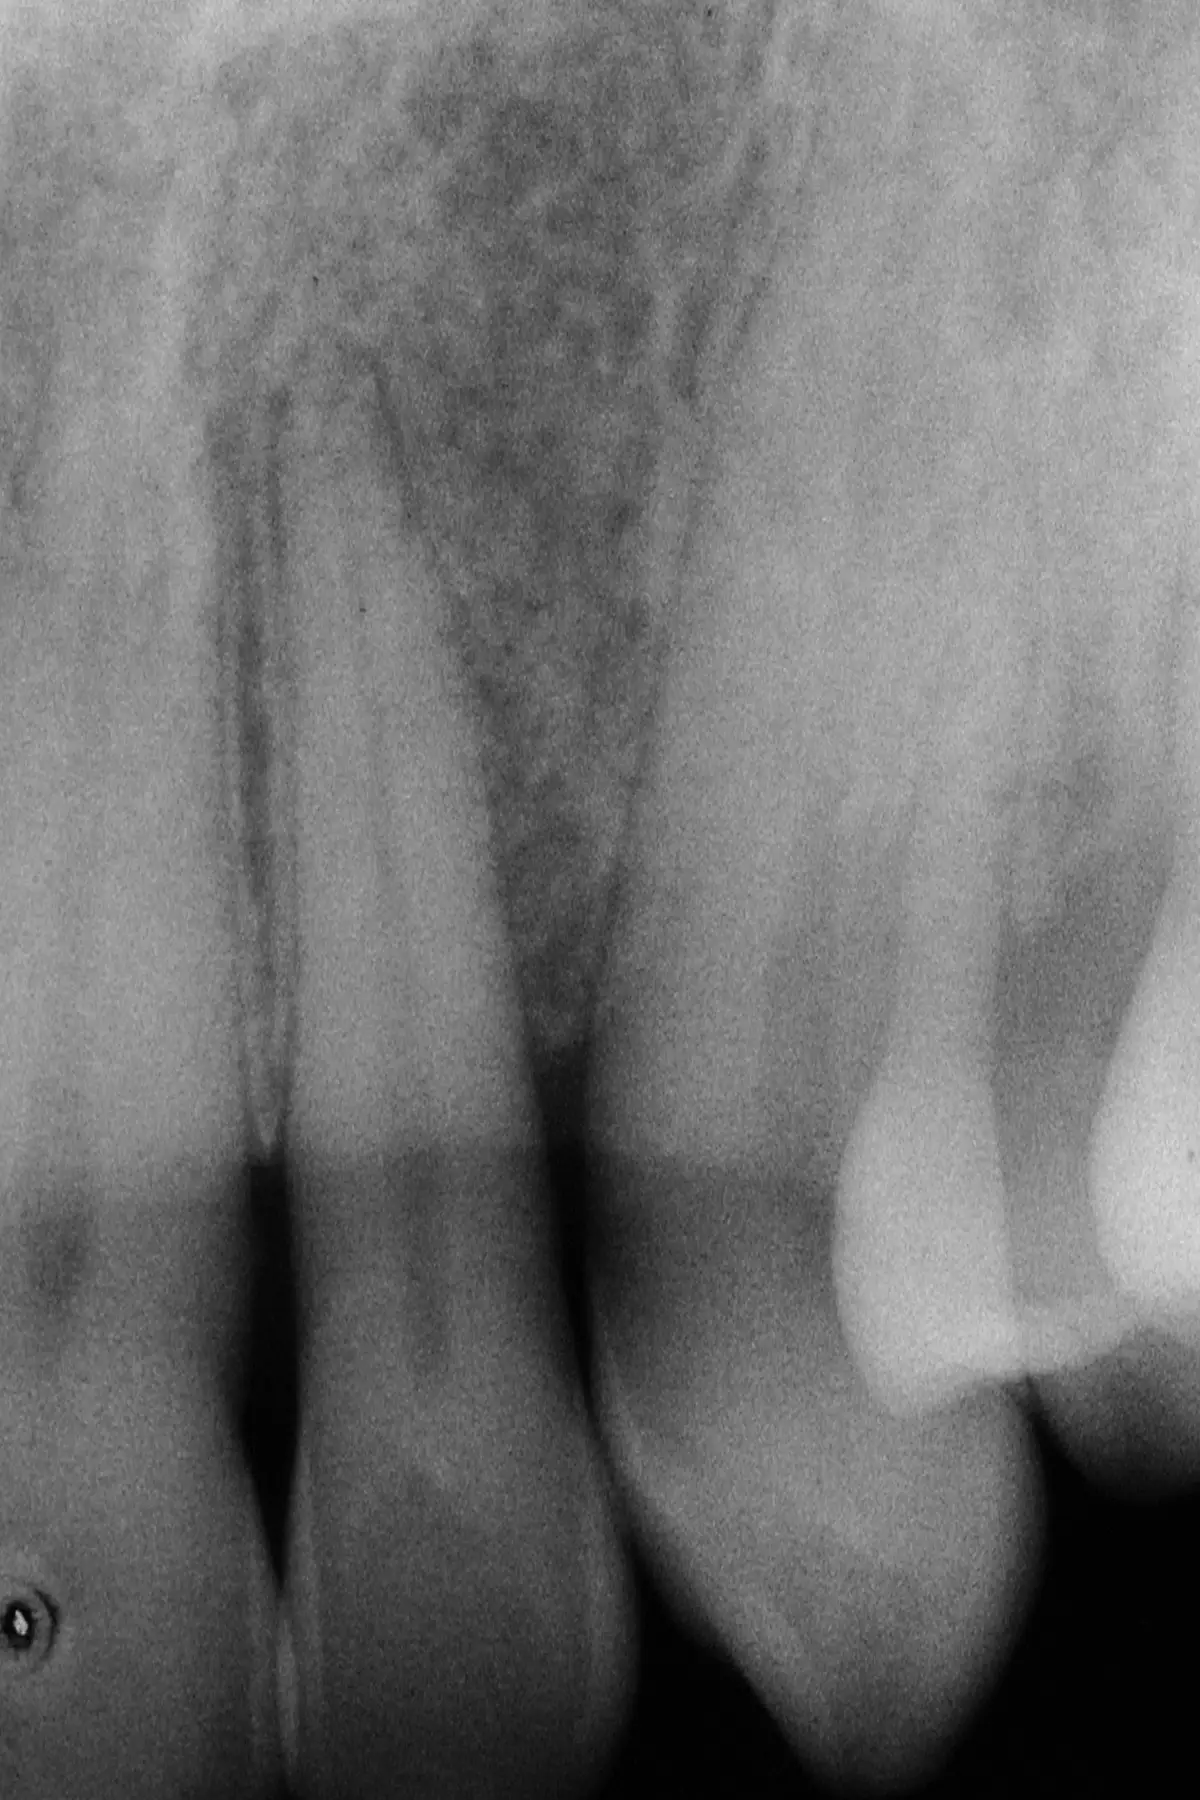

Bone Graft

before

after